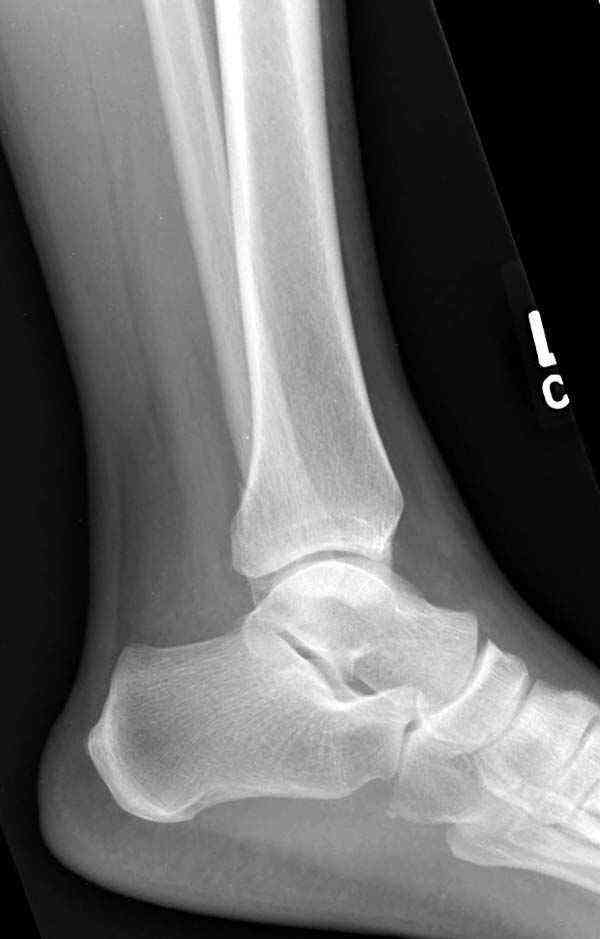

Достаточно быстрое восстановление функции.В октябре 2009г-почувствовала боль,в области рубца над гайкой открылся свищ.На Р-граммах-консолидация переломов и смещение гайки по стяжке.10.11.2009г-конструкции удалены,санация,заживление ран.В настоящее время пациентку ничего не беспокоит.На операции-раскручивание гайки-болталась на конце стяжки.Вопросы:какой механизм раскручивания и что я неправильно сделал?Свои версии:1)в области синдесмоза успела образоваться рубцовая ткань,которая при движении в суставе"пружинила",поскольку голеностопный сустав является спиральным, то и биомеханика подобна кривошипному механизму.2)Реконструктивная пластина не "реконструировалась" по форме лодыжки.Наложил,как есть.То есть подпружинивала сама пластина.Ну,это мои догадки.Что нужно,чтобы избегать впредь таких,пусть и не "страшных"осложнений:Рассверливать через лодыжку область синдесмоза?Ставить шайбу-гровер?Тщательно моделировать пластину?Прилагаю сравнительные снимки-сразу после операции и перед удалением конструкции.

Раз ,есть желание посмотреть другую проекцию выкладываю-ну лучшего качества нет...

Здесь несколько частных случаев: перелом голеностопа со сравнительными снимками и разрыв синдесмоза, а также медиальная Hook пластина.